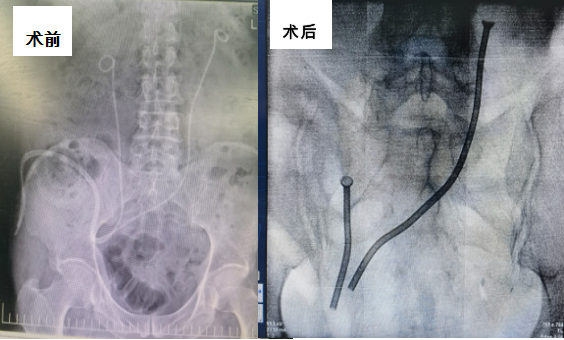

孙羿主任联合北京朝阳医院张军晖主任在术前充分评估,针对术中可能出现的各种情况充分论证、准备,在确保万无一失的情况下于2月19日开展手术。由于患者既往行膀胱癌根治术,吻合口位置特殊,情况复杂,术中反复调试,不断修正,直至确保金属支架能完全覆盖狭窄全段,术后不会发生再狭窄可能。在两位专家的通力合作下手术顺利完成,金属支架位置良好。患者术后引流良好,未出现任何不良反应。